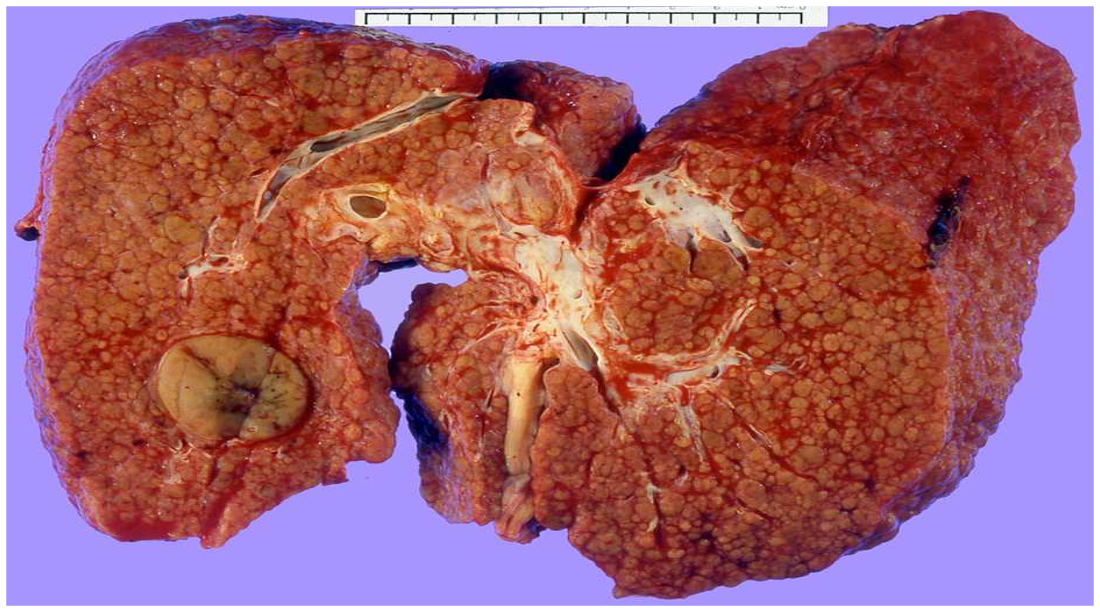

Gross HCC - Liver Cirrhosis (HBV – HCV)

cirrhotic, tumour round homogenous on right lobe

Huge hepatocellular carcinoma in the right lobe of the liver